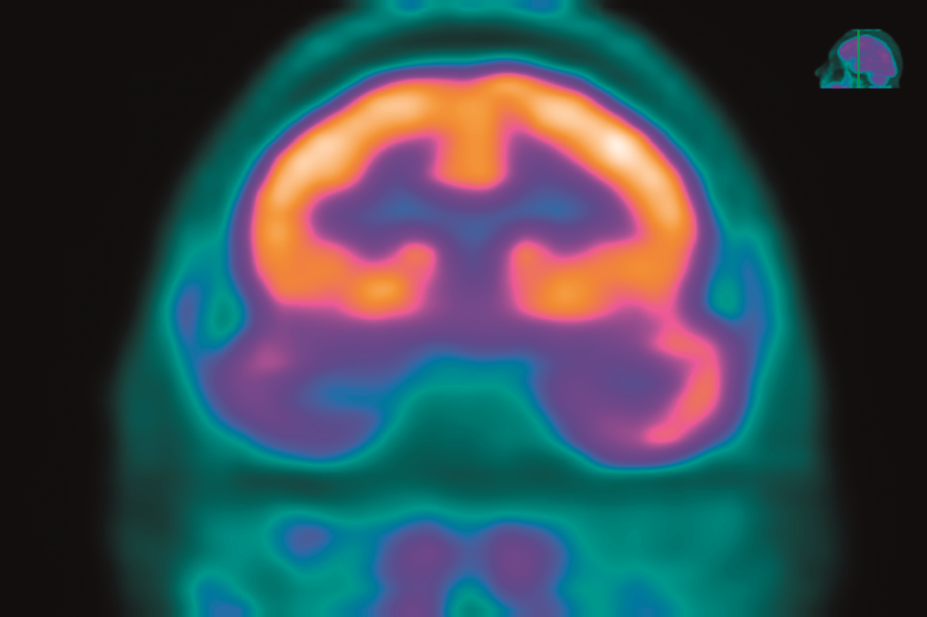

癲癇發(fā)作是由某些腦細胞(神經元)的異常活動引起的。手術的類型取決于開始癲癇發(fā)作的神經元的位置和患者的年齡。手術類型包括:

1、切除手術:常見的癲癇手術,即是切除大腦的一小部分。外科醫(yī)生切除發(fā)生癲癇發(fā)作的大腦區(qū)域的腦組織,通常是腫瘤、腦損傷或畸形的部位。切除手術常在其中一個顳葉上進行,顳葉是一個控制視覺記憶、語言理解和情緒的區(qū)域。

2、激光間質熱療 (LITT):是一種侵入性較小的手術,它使用激光來精確定位和損害一小部分腦組織。磁共振成像 (MRI) 用于引導外科醫(yī)生使用的激光。

3、深部腦刺激:即是使用一種設備長期植入大腦深處來釋放定期定時的電信號,損害異常的、誘發(fā)癲癇的活動。該過程也由MRI指導。發(fā)送電脈沖的發(fā)生器被植入胸部。

4、胼胝體切開術:這是一種完全或部分切除連接大腦左右兩側神經的部分大腦(胼胝體)的手術。這通常用于經歷從大腦一側蔓延到另一側的異常大腦活動的兒童。

5、半球切除術:這是一種去除大腦(大腦皮層)折疊灰質一側(半球)的手術。這種手術通常適用于在一個半球的多個部位出現(xiàn)癲癇發(fā)作的兒童,通常是出生時或嬰兒早期出現(xiàn)的疾病的結果。

6、功能性大腦半球切除術:這是一種主要用于兒童的手術,它在不去除大腦的實際部分的情況下去除連接神經。